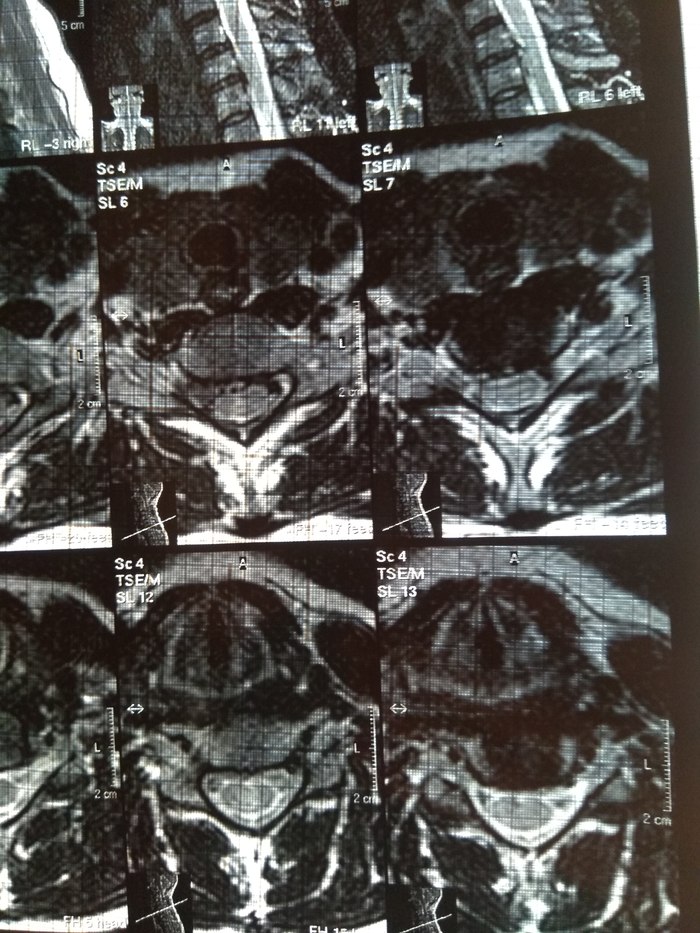

У подруги случилась проблема, тянула с визитом к врачу и в итоге потеряла сознание, вызывали скорую и направили к неврологу. Онемение пальцев на правой руке, сильные боли до судорог и потери сознания. В итоге невролог направил на МРТ и к нейрохирургу, выписали ношение ортопедического воротника, 2 вида уколов и таблетки, названия навскидку не помню. Сказали если через 10 дней не полегчает, то на операцию. Сегодня 5й день, никаких улучшений, рука с каждым днем выше немеет, но подвижность пока в норме. В день по 2-3 раза колет кетонал. Я вот переживаю как бы рука не отказала. Такое может случиться?